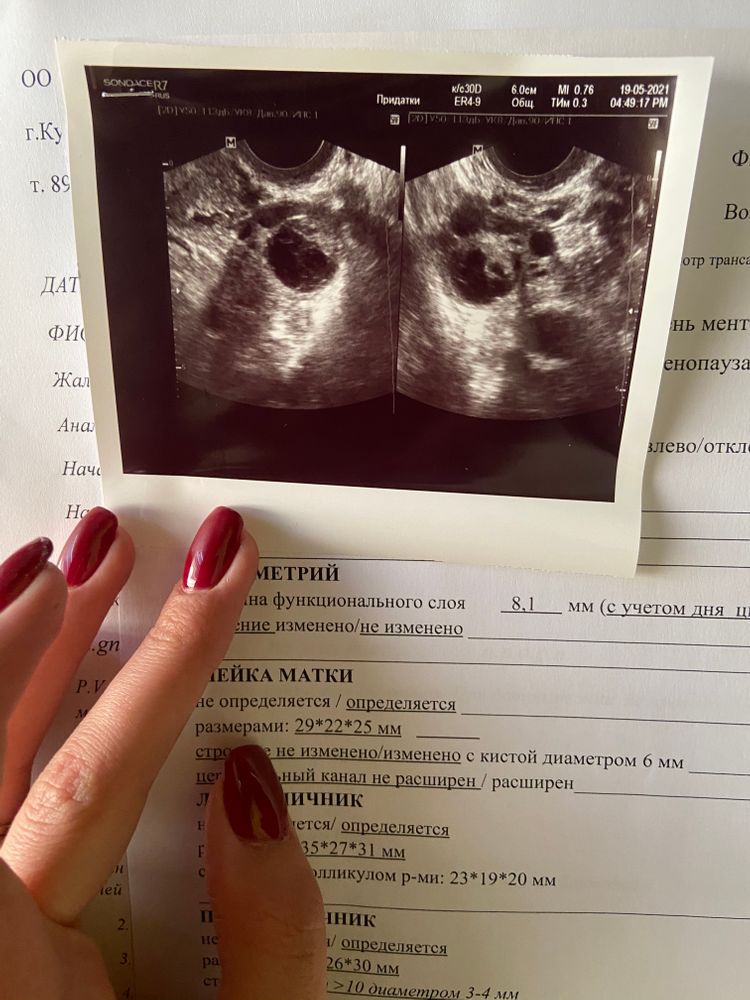

Желтое тело или доминантный фолликул???

Узист сказала, что это ДФ, и овуляция не произошла, хотя свободная жидкость в малом тазу 10мл, сегодня ночью болел низ живота, и день овуляции был... ни у кого нету ГК онлайн?

ЖТ и ДФ нельзя перепутать на узи, если врач хоть курс университета закончил. У ЖТ есть кровоток. У ДФ его нет.

Littetbe, жидкость не указывает, что фолликул лопнул. Но что овуляция запустилась - может. Тест показывает не саму овуляцию, а всплеск ЛГ, который происходит до неё. После положительного теста овуляция через 24-48 часов. То есть вам лучше завтра сходить ещё раз на узи, если хотите знать 100%. По снимкам просто ,к сожалению, не понятно ЖТ это или ДФ. Может быть и перепутала она, тогда к этому врачу лучше не возвращаться никогда. Про поликистоз бред, по одному только узи его не ставят. Могут поставить под вопросом, далее смотрят гормоны и на узи в динамике. Так что может и врач была не компетентной очень.

Софья, а узист говорит что большой фолликул сильно, и не лопнул он, а так же продолжит расти, и возможно перейдёт в кисту... хотя свободная жидкость есть

Littetbe, на допплере смотрели кровоток? Хотя если он только лопнул и ещё не успел сформироваться в ЖТ, кровотока там и не будет. Может в саму овуляцию попали во время узи